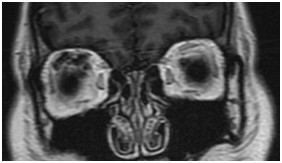

颞骨及耳(病例-前庭导水管扩大)